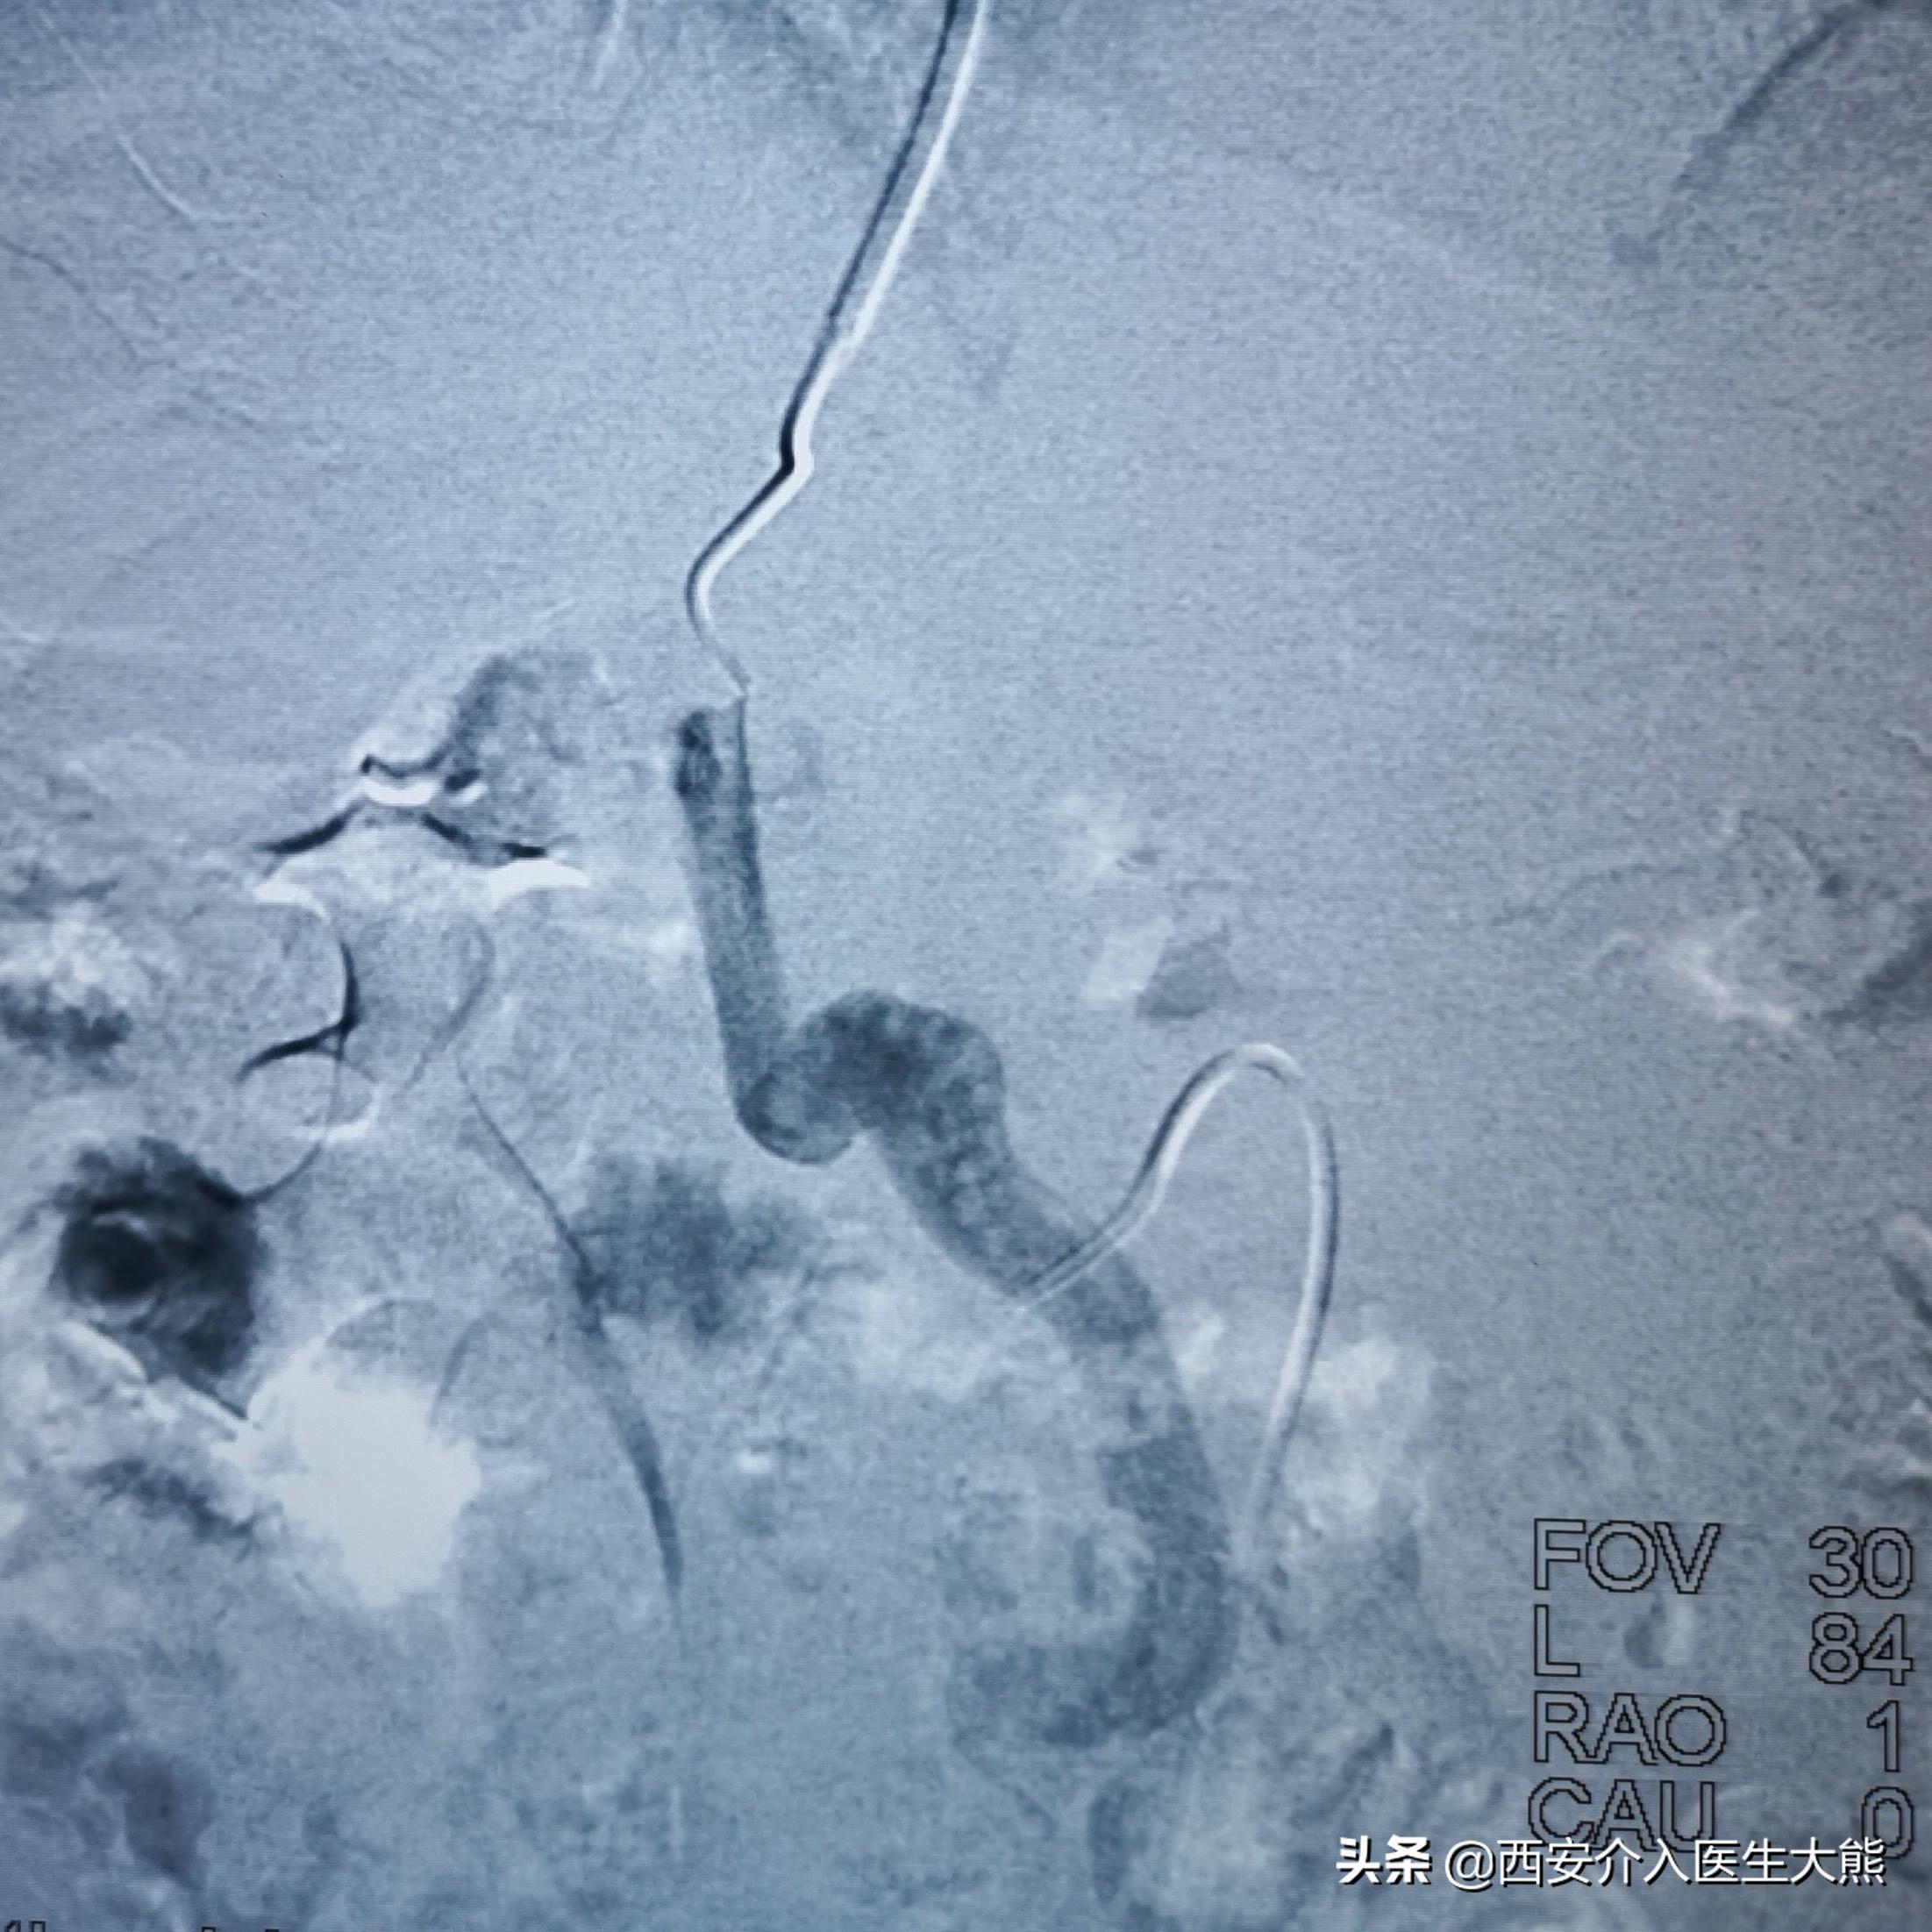

3.术中DSA:

扩张的脐静脉

扩张的没静脉和胃冠状静脉

扩张的胃冠状静脉

TIPS和食管胃底静脉栓塞术后

这名患者的治疗过程就符合该治疗策略。术前的CT平扫已经显示极度扩张的胃冠状静脉,这在DSA影像上得到证实。2018年患者第二次出血时做的增强CT上已经显示出患者的胃冠状静脉扩张。此时,已经具有行TIPS的指征。在经过3年的变化后,病情是急剧加重。如果出血剧烈、生命体征不平稳,或各种原因导致不能行急诊胃镜的情况下,不要错过TIPS降低门脉压力的机会。